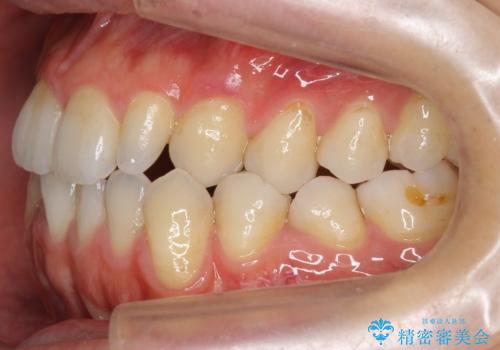

受け口 絶対に顎の手術はしたくない

- 受け口を主訴に来院。

下あごが大きく、顎の手術を含めた矯正をおすすめしましたが、手術は怖いので絶対にしたくないとのことでした。

歯並びのみを治す矯正は難しく、長期にわたる治療になるとご説明しました。

かみしめもあり、骨も固く、歯根も長いためなかなか歯が動かず、患者様も治療する側も忍耐を要する長期戦となりました。